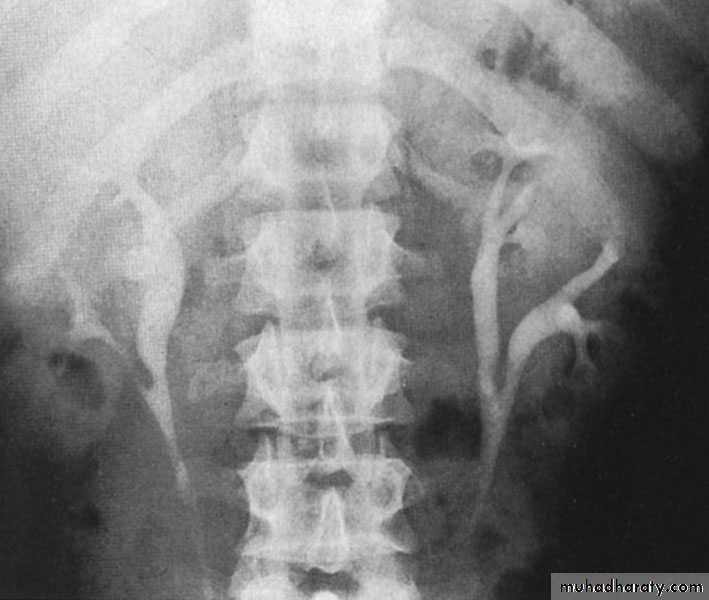

Crossed Renal Ectopia With and Without FusionHorseshoe Kidney

found in 1:1000 necropsies an is commoner in men.probably the most common of all renal fusion anomalies

The anomaly consists of two distinct renal masses lying

vertically on either side of the midline and connected at

their respective lower poles by a parenchymatous or fibrous

isthmus that crosses the midplane of the body.

Fusion of the renal masses early in embryonic life, so its ascent

will be impeded by inferior mesenteric artery.

The kidneys are low located, mal rotated and pelves lie anteriorly

Symptom When present, they are related to complications like hydronephrosis, infection, or calculus formation

Diagnosis ultrasound, IVU, CT scan

Treatment:

-Medical: pain relief and to control infection-Surgical: stone removal, PUJ stenosis correction and isthmus division in cases of

-operations on the aorta

Prognosis usually they have normal life.